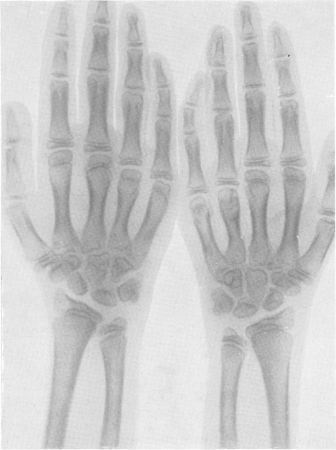

Fig. 274. Osteochondrodystrofia la o fată de 9 ani.

Raza X a regiunii ambelor articulații genunchiului. Fibula este la o înălțime normală. Trebuie să presupunem că, atunci când osteohondrodistrofii scurtarea oaselor și prioskhodit, în esență, prin reducerea înălțimii epifizei, nu scurtarea metadiafiză. Contururile exterioare ale epifizelor sunt zdrobite și chiar erodate. Nucleul separat de osificare este împărțit, împărțit în părți, fragmentat, adică apar o mulțime de insule neregulate fără formă de osificare. Când epifizele se dezvoltă odată cu vârsta, ele "maturează", structura lor este încă oarecum ordonată, dar deformarea rămâne stabilă și ireversibilă. Late și subliniate sub forma benzilor dense ale zonei de osificare preliminară (figura 274). Oasele tubulare mici au fost, de asemenea, schimbate. Falajele sunt ușor scurtate și îngroșate, substanța lor spongioasă are o structură specială de plasă fină (figurile 275 și 276). Rata de osificare în seria noastră de cazuri este oarecum încetinită, nucleele de osificare în cazuri normale apar cu o mică întârziere. Pseudoepifizele se pot dezvolta. De aceea, la copiii mici, intervalele dintre metafiză ale oaselor opuse sunt mari - raze X articulate, uneori aproape de două ori mai largi decât cele normale. Fuziunea finală a epifizelor cu diafiză are loc cu deviații de la timpul normal în ambele direcții, uneori cu fluctuații mari. Modificări deosebit de mari se observă la copiii de vârstă școlară, apoi mai devreme, apoi mai târziu, în oasele articulației șoldului (Figurile 277 și 278). Capul epifizal al coapsei se poate să aștepte mult timp. Apărând, ea la o anumită vârstă tinerească dobândește o formă și o structură neregulată. Se mărește în mărime, aplatizează și se extinde, se împarte în multe aglomerări neregulate în formă de cartiere terestre.

Fig. 275. Același pacient. X-ray de mâini și zone de articulații încheietura mâinii.